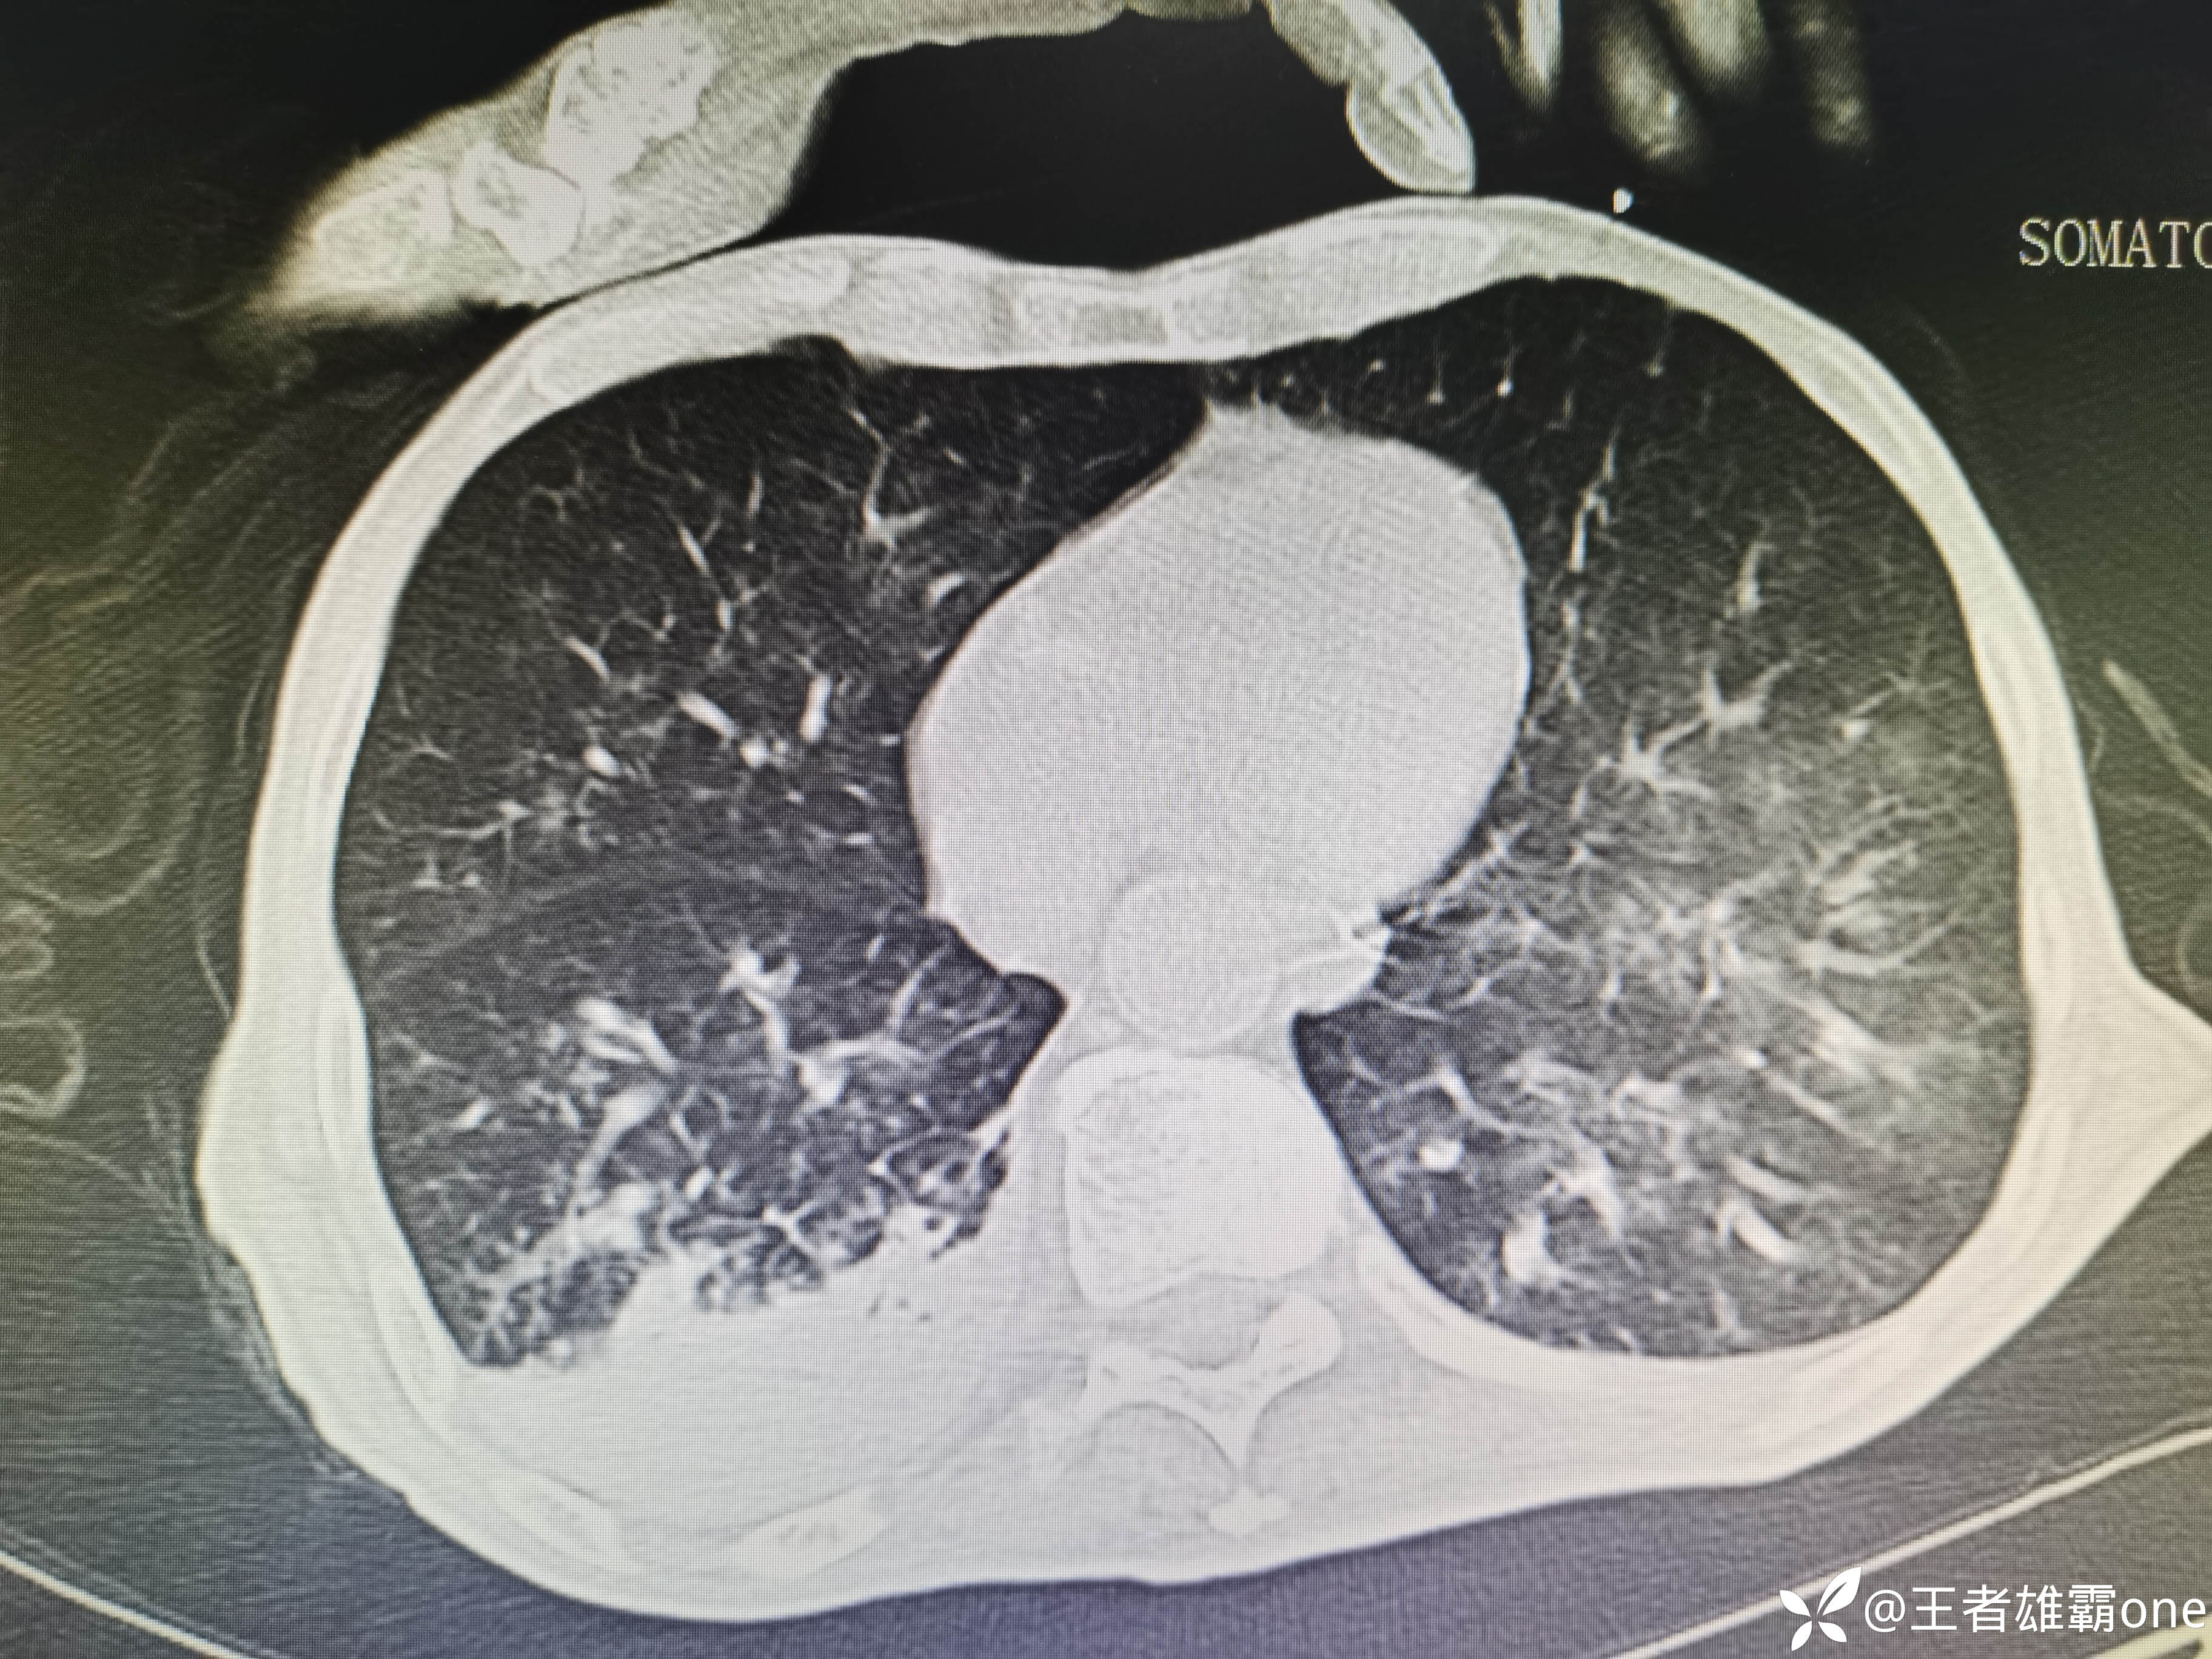

入院时胸部CT:

具体图片: